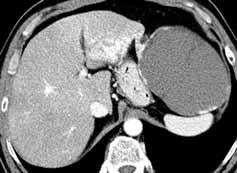

Rycina 38.39. (A–C)

Ogniskowy rozrost guzkowy (FNH – focal nodular hyperplasia)